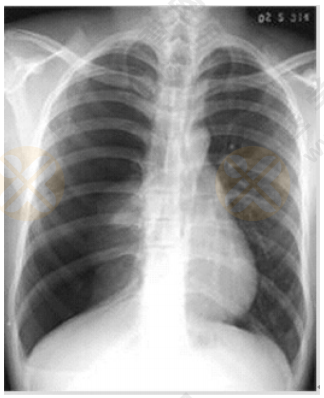

2022年中西医执业医师实践技能【西医临床答辩】02号题:根据下图所给X线片分析临床意义